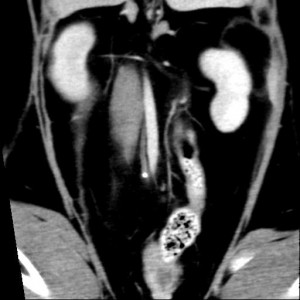

今回は左右の尿管結石であり、CT検査から右では尿管中央にて結石があり腎盂にも小さな結石が確認された。左では近位の蛇行した尿管に小さな結石があり腎盂に多数の結石を確認。

腎盂での結石の存在、尿管結石が複数あること、結石の存在箇所より遠位が狭窄している可能性が高いことから尿管ステントの適応と判断しました。

画面左が右の尿管結石の位置での断面で、右が左尿管近位の蛇行した尿管内の結石を示している像です。